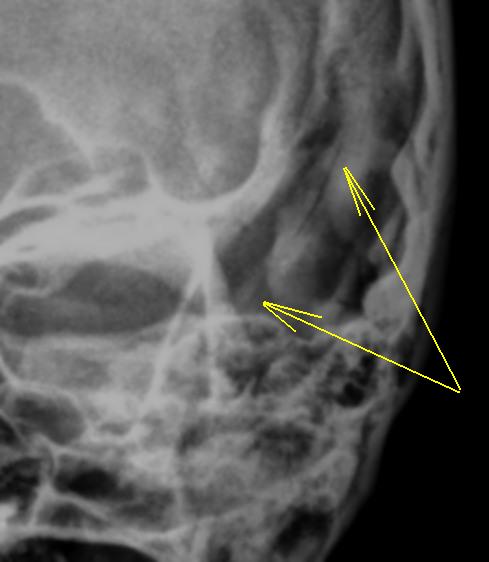

На боковой рентгенограмме нуждаются во внимании, на мой взгляд, помеченные стрелками "линии".

Вызывает сомнения и медиальный край орбиты.

Провокация № 1. Чем объяснить "нечеткость" задних клиновидных отростков?